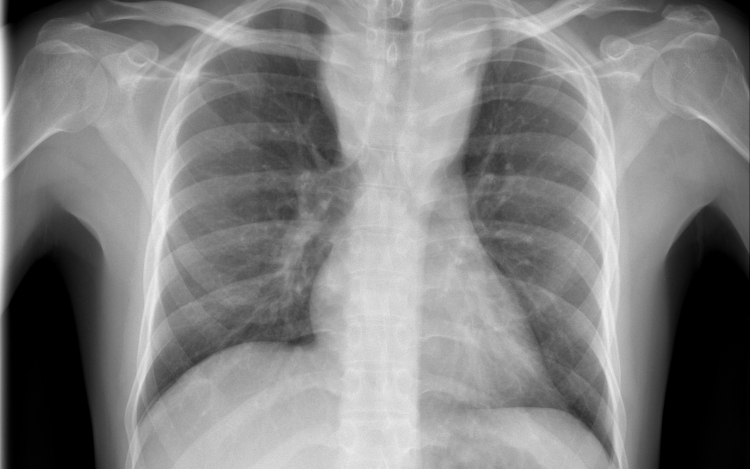

Magyarországon halnak meg a legtöbben tüdőrákban az EU-ban

Az Európai Unióban Magyarországon a legmagasabb, az összes halálok között 27 százaléknyi a tüdőrák okozta halálozások aránya - hangzott el az M1 aktuális csatorna csütörtöki műsorában.